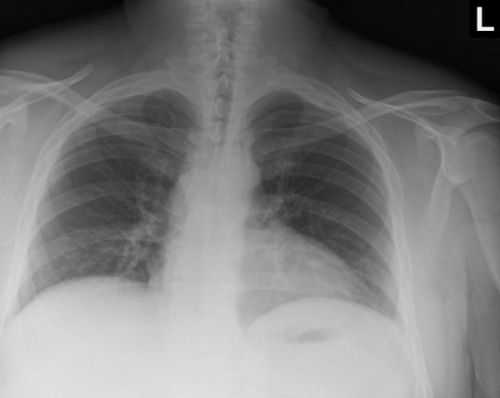

Tool to train medical student's eyes as to what a normal chest x-ray looks like, with over 500 consecutive normal images.